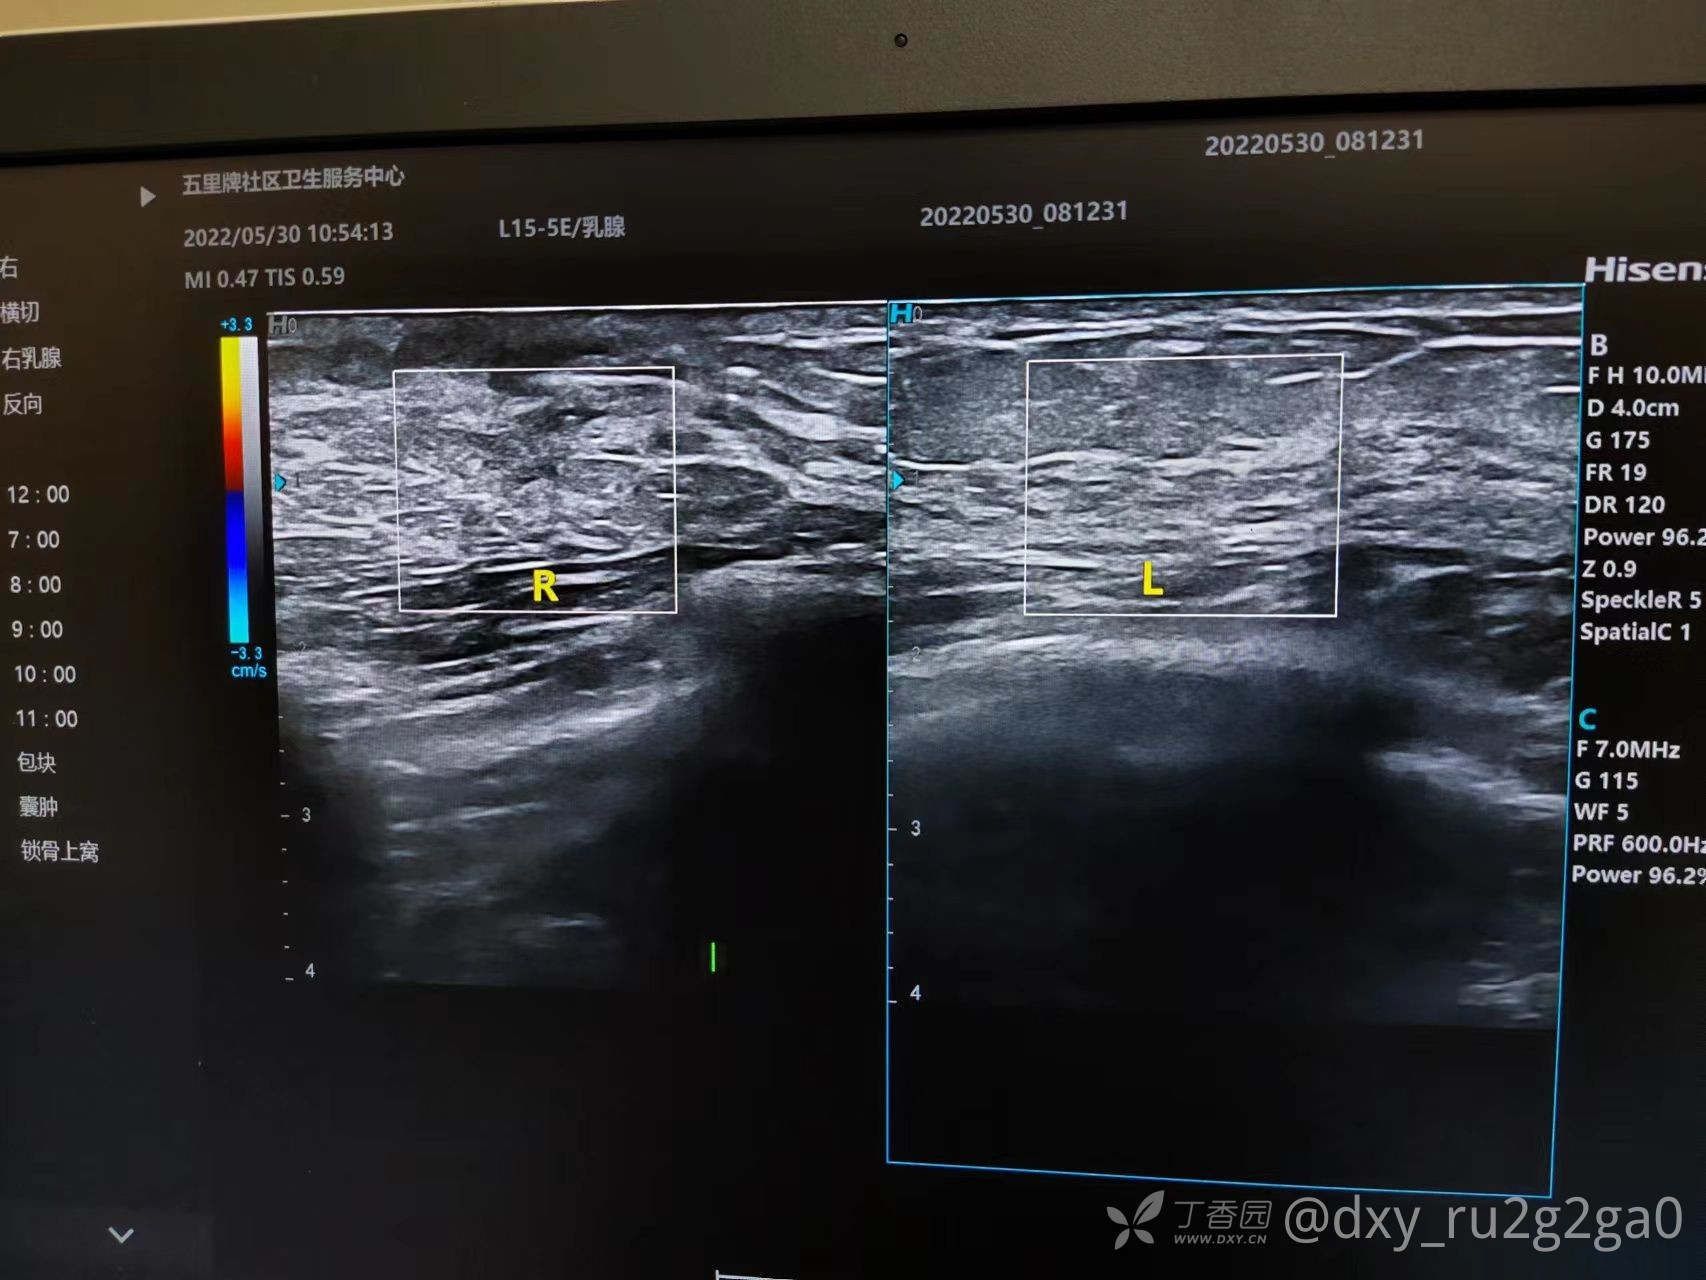

该病例21岁未婚 右胸偶感疼痛 如针刺样 触诊有肿块

img